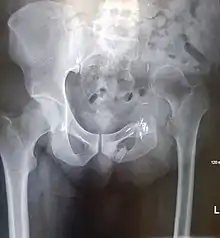

Prior to performing a hemipelvectomy, surgeons must possess detailed knowledge of the pelvic anatomy and its relation to the pelvic tumor.[1] Imaging studies such as conventional radiography, computed tomography, and magnetic resonance imaging help the surgeon visualize the anatomy and its relationship to the local pathology.[1] Surgical oncology techniques are utilized when resecting tumors of the pelvis.[1] Such techniques ensure that adequate resection margins are obtained at the time of surgery to minimize tumor recurrence.[1]

The Enneking and Dunham classification system was developed in 1978 to aid surgeons in characterizing pelvic resections.[1][3][4] This classification scheme breaks down pelvic resections into 3 subtypes: Type I, Type II, and Type III.[1][3][4] Type I resections involve removal of the ilium.[1][3][4] Type II resections involve removal of the peri-acetabular region.[1][3][4] Type III resections involve removal of the ischial and/or pubic region.[1][3]